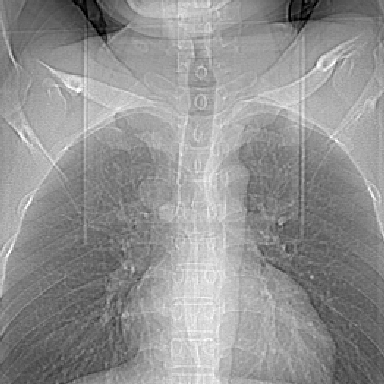

m 30 右胸痛10年

右上后纵隔旁软组织肿块影,与肺界面光滑,与胸壁呈钝角相交,提示肺外病变。位于肋骨下缘,边缘清楚,呈三角样指向与右侧椎间孔,但并示进入椎间孔;与对侧神经根对比,属同一走行方向。

考虑后纵膈良性肿瘤,神经源性肿瘤可能大。

右上后纵隔脊柱旁见长椭圆形肿块,边界光整,与胸壁呈钝角。周围骨质未见异常。

考虑、1、后纵隔神经源性肿瘤;

2、不除外单发胸膜间皮瘤。